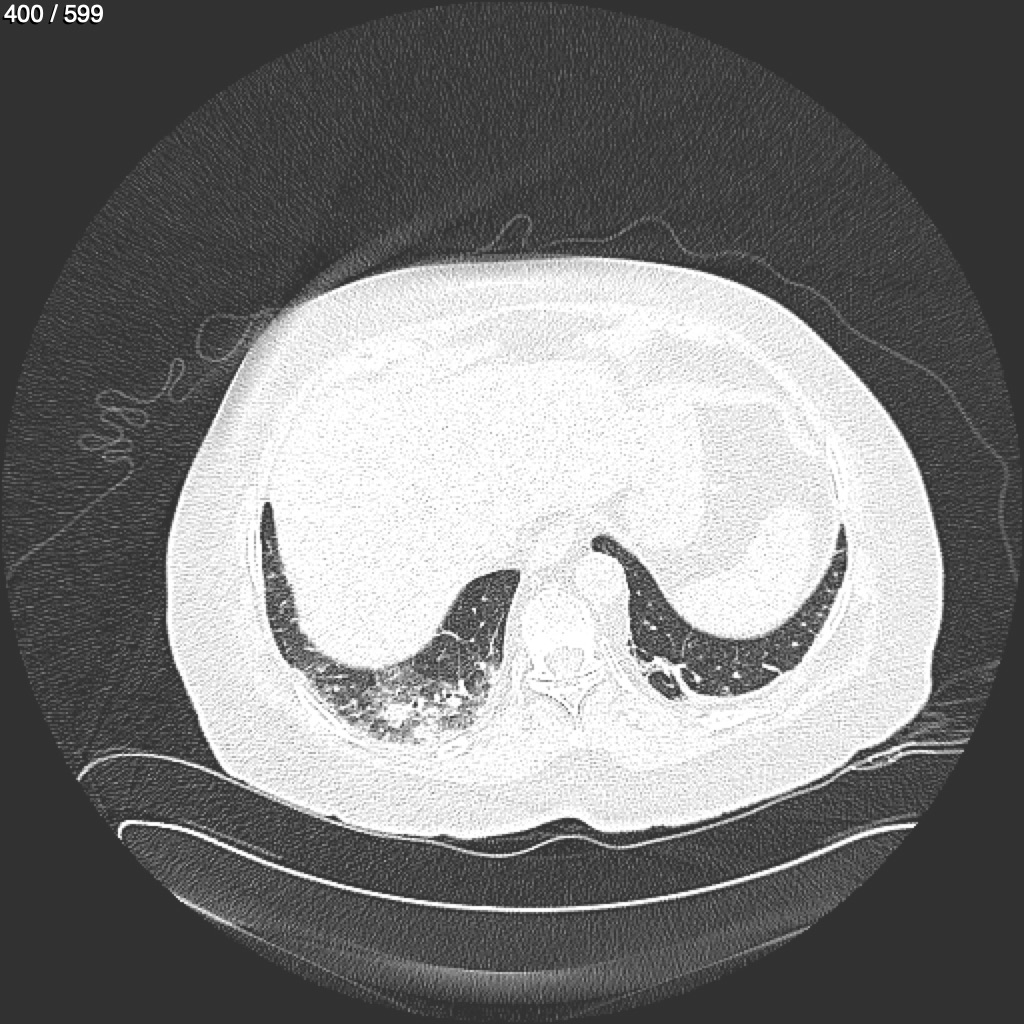

Home G​l​o​r​i​a​ ​G​l​a​d​y​s​ ​B​e​a​s​l​e​y​ ​-​ ​T​ó​r​a​x​ ​T​o​r​a​x​_​S​i​m​p​l​e​ ​(​A​d​u​l​t​o​)